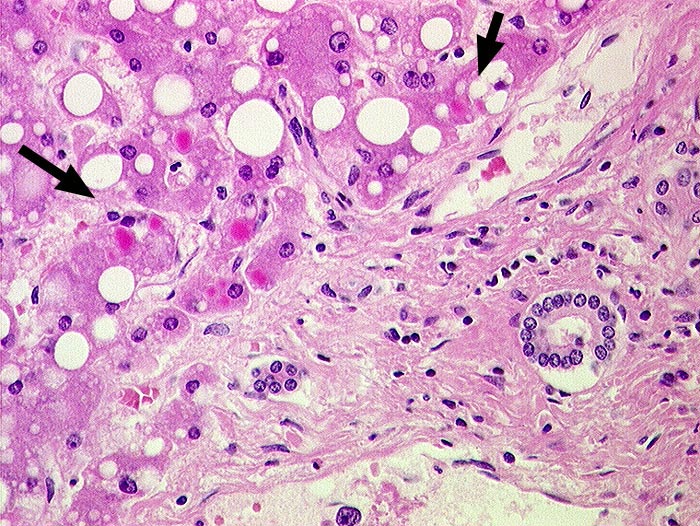

AP/ Leber bei alpha-1-Antitrypsinmangel

Leber bei alpha-1-Antitrypsinmangel